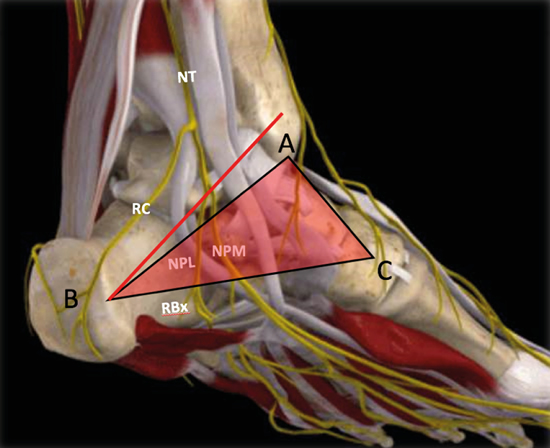

No obstante, la visualización de los nervios plantar medial y plantar lateral es más evidente cuando se avanza hacia distal. Para ello se mantiene la sonda en eje corto (Figura 13) tomando como referencia la tuberosidad posterior del calcáneo, de donde parten el eje de Dellon-Mackinnon4 y el triángulo de Heimkes (área entre tuberosidad del calcáneo, el vértice del maléolo medial y el navicular)8 (Figura 12).

Figura 13. Línea de Dellon-Mackinnon (A-B) y triángulo de Heimkes (A-B-C). Se observan el nervio tibial (NT) y las ramas calcánea (RC), el nervio plantar lateral (NPL), el nervio plantar medial (NPM) y la rama de Baxter (RBx). Imagen modificada de la App Ankle & Foot Pro III.